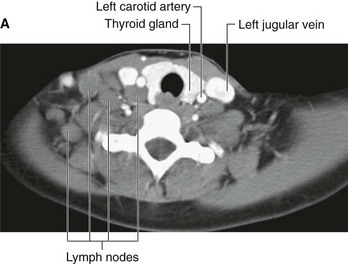

In the clinic Lymph nodes

Lymph nodes are efficient filters and have an internal honeycomb of reticular connective tissue filled with lymphocytes. These lymphocytes act on bacteria, viruses, and other bodily cells to destroy them. Lymph nodes tend to drain specific areas, and if infection occurs within a drainage area, the lymph node will become active. The rapid cell turnover and production of local inflammatory mediators may cause the node to enlarge and become tender. Similarly, in patients with malignancy the lymphatics may drain metastasizing cells to the lymph tender. Similarly, in patients with malignancy the lymphatics may drain metastasizing cells to the lymph nodes. These can become enlarged and inflamed and will need to be removed if clinically symptomatic.

Lymph nodes may become diffusely enlarged in certain systemic illnesses (for example, viral infection), or local groups may become enlarged with primary lymph node malignancies, such as lymphoma (Fig. 1.32).

image image

Fig. 1.32 A. This computed tomogram with contrast, in the axial plane, demonstrates the normal common carotid arteries and internal jugular veins with numerous other nonenhancing nodules that represent lymph nodes in a patient with lymphoma. B. This computed tomogram with contrast, in the axial plane, demonstrates a large anterior soft-tissue mediastinal mass that represents a lymphoma.